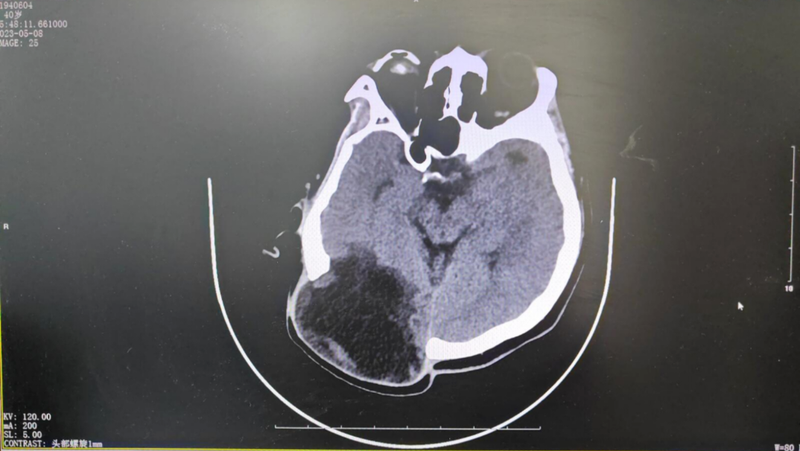

患者男性39歲,因腦膜瘤于當(dāng)?shù)蒯t(yī)院行經(jīng)枕開顱腫瘤切除術(shù),術(shù)后12天發(fā)現(xiàn)手術(shù)切口膿性分泌物,再次行右枕開顱術(shù)后切口感染探查清創(chuàng)術(shù)+去骨瓣術(shù),術(shù)后恢復(fù)良好出院。患者為行顱骨修補(bǔ)來我科。患者右枕部顱骨缺損面積較大,且皮下積液膨出,手術(shù)整形修補(bǔ)指征明確,完善術(shù)前檢查后行顱骨修補(bǔ)術(shù),手術(shù)順利,術(shù)后恢復(fù)好。